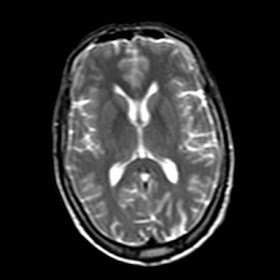

A 40 years old man with electric current like pain in left side of his face since 4 years